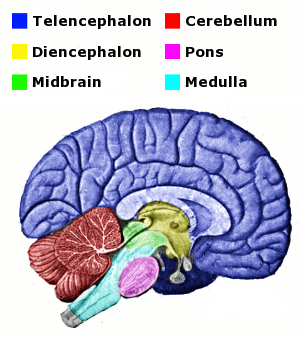

Medulla Oblongata: What It Is, Function & Anatomy

The Anatomy of the Medulla Oblongata

The Medulla Oblongata - Internal Structure - Vasculature

Medulla Oblongata Location, Function, and Features

Medulla oblongata – Lancaster Glossary of Child Development

Pons - Wikipedia

Medulla Oblongata - The Definitive Guide | Biology Dictionary

Medulla oblongata - Wikipedia

The Medulla Oblongata and Pons

Medulla - The Brain and Psychology

Medulla Oblongata: Definition, Structure And Functions